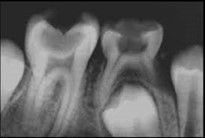

Estudio utilizado para determinar la posición de un diente o un objeto en los maxilares. Las principales aplicaciones son para analizar cuerpos extraños, dientes impactados, dientes no erupcionados, raíces retenidas, posiciones radiculares, Fracturas maxilares, etc.